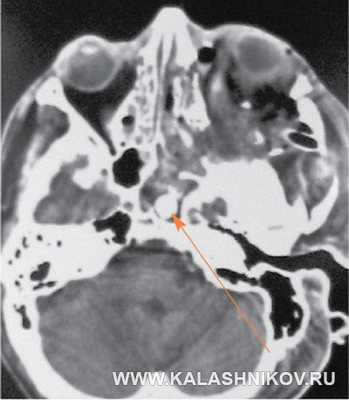

КТ головы пострадавшего М-ва на уровне расположения инородного тела в основной пазухе черепа. Стрелкой указано положение пули патрона 9 Р.А.

На компьютерной томограмме (КТ) головы в основной пазухе выявлено внедрившееся инородное тело округлой формы диаметром 9 мм, идентифицированное при последующей хирургической обработке раны, как пуля патрона 9 Р.А. (ил. 6)